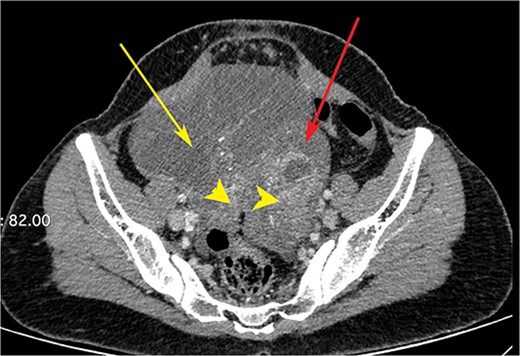

A woman in her early 30s, with no prior morbidities, presented with fullness in the epigastrium and a weight loss of 5 kg in the past month. She had a regular menstrual history and a history of two full-term normal deliveries. Her last child was born 5 years ago. She had no relevant medical history. On examination, her pulse was 120 beats per minute, blood pressure was 160/80 mm of mercury, respiratory rate was 20 per minute, and Glasgow coma scale was 15. Hernial orifices were normal. Abdominal and chest examinations were normal. There was no lymphadenopathy. Examinations of skin, skull, and spine were normal. There was nothing significant on per rectal and per vaginal examination. A PA X-ray of the chest showed normal findings. Blood investigations showed: haemoglobin: 10.5 g/dl, total leucocyte: 7.4 × 100/l, serum creatinine: 0.72 mg/dl, random blood sugar: 86 g/dl, alanine transaminase: 24 U/l, aspartate transaminase: 16 U/l, alkaline phosphatase: 35 U/l, and total bilirubin: 0.8 mg/dl. Esophagogastroduodenoscopy was performed, which showed erythema, loss of rugosity and an extra mucosal bulge at the antrum; mucosal biopsies were positive for malignancy (Fig. 1). Tumour markers CA-125 and CA-19-9 were normal. The distal stomach did not expand with insufflation, suggesting diffuse infiltration. Serology testing of Helicobacter pylori was negative. An abdominal CT scan showed a bilateral ovarian cyst with solid components and gastric antral wall thickening (Figs 2 and 3). There was no lymphadenopathy, liver spleen, urinary bladder kidney lesions, or ascites. The diagnosis was LP of the stomach with bilateral Krukenberg tumours (KT). A diagnostic laparoscopy showed no peritoneal disease on multiple biopsies and washes. It also showed no gastric serosal infiltration, and it was possible to get an R0 resection.

CT scan of the abdomen showing right ovarian cyst (yellow arrow), left ovarian cyst (red arrow) with solid elements within (arrow heads).